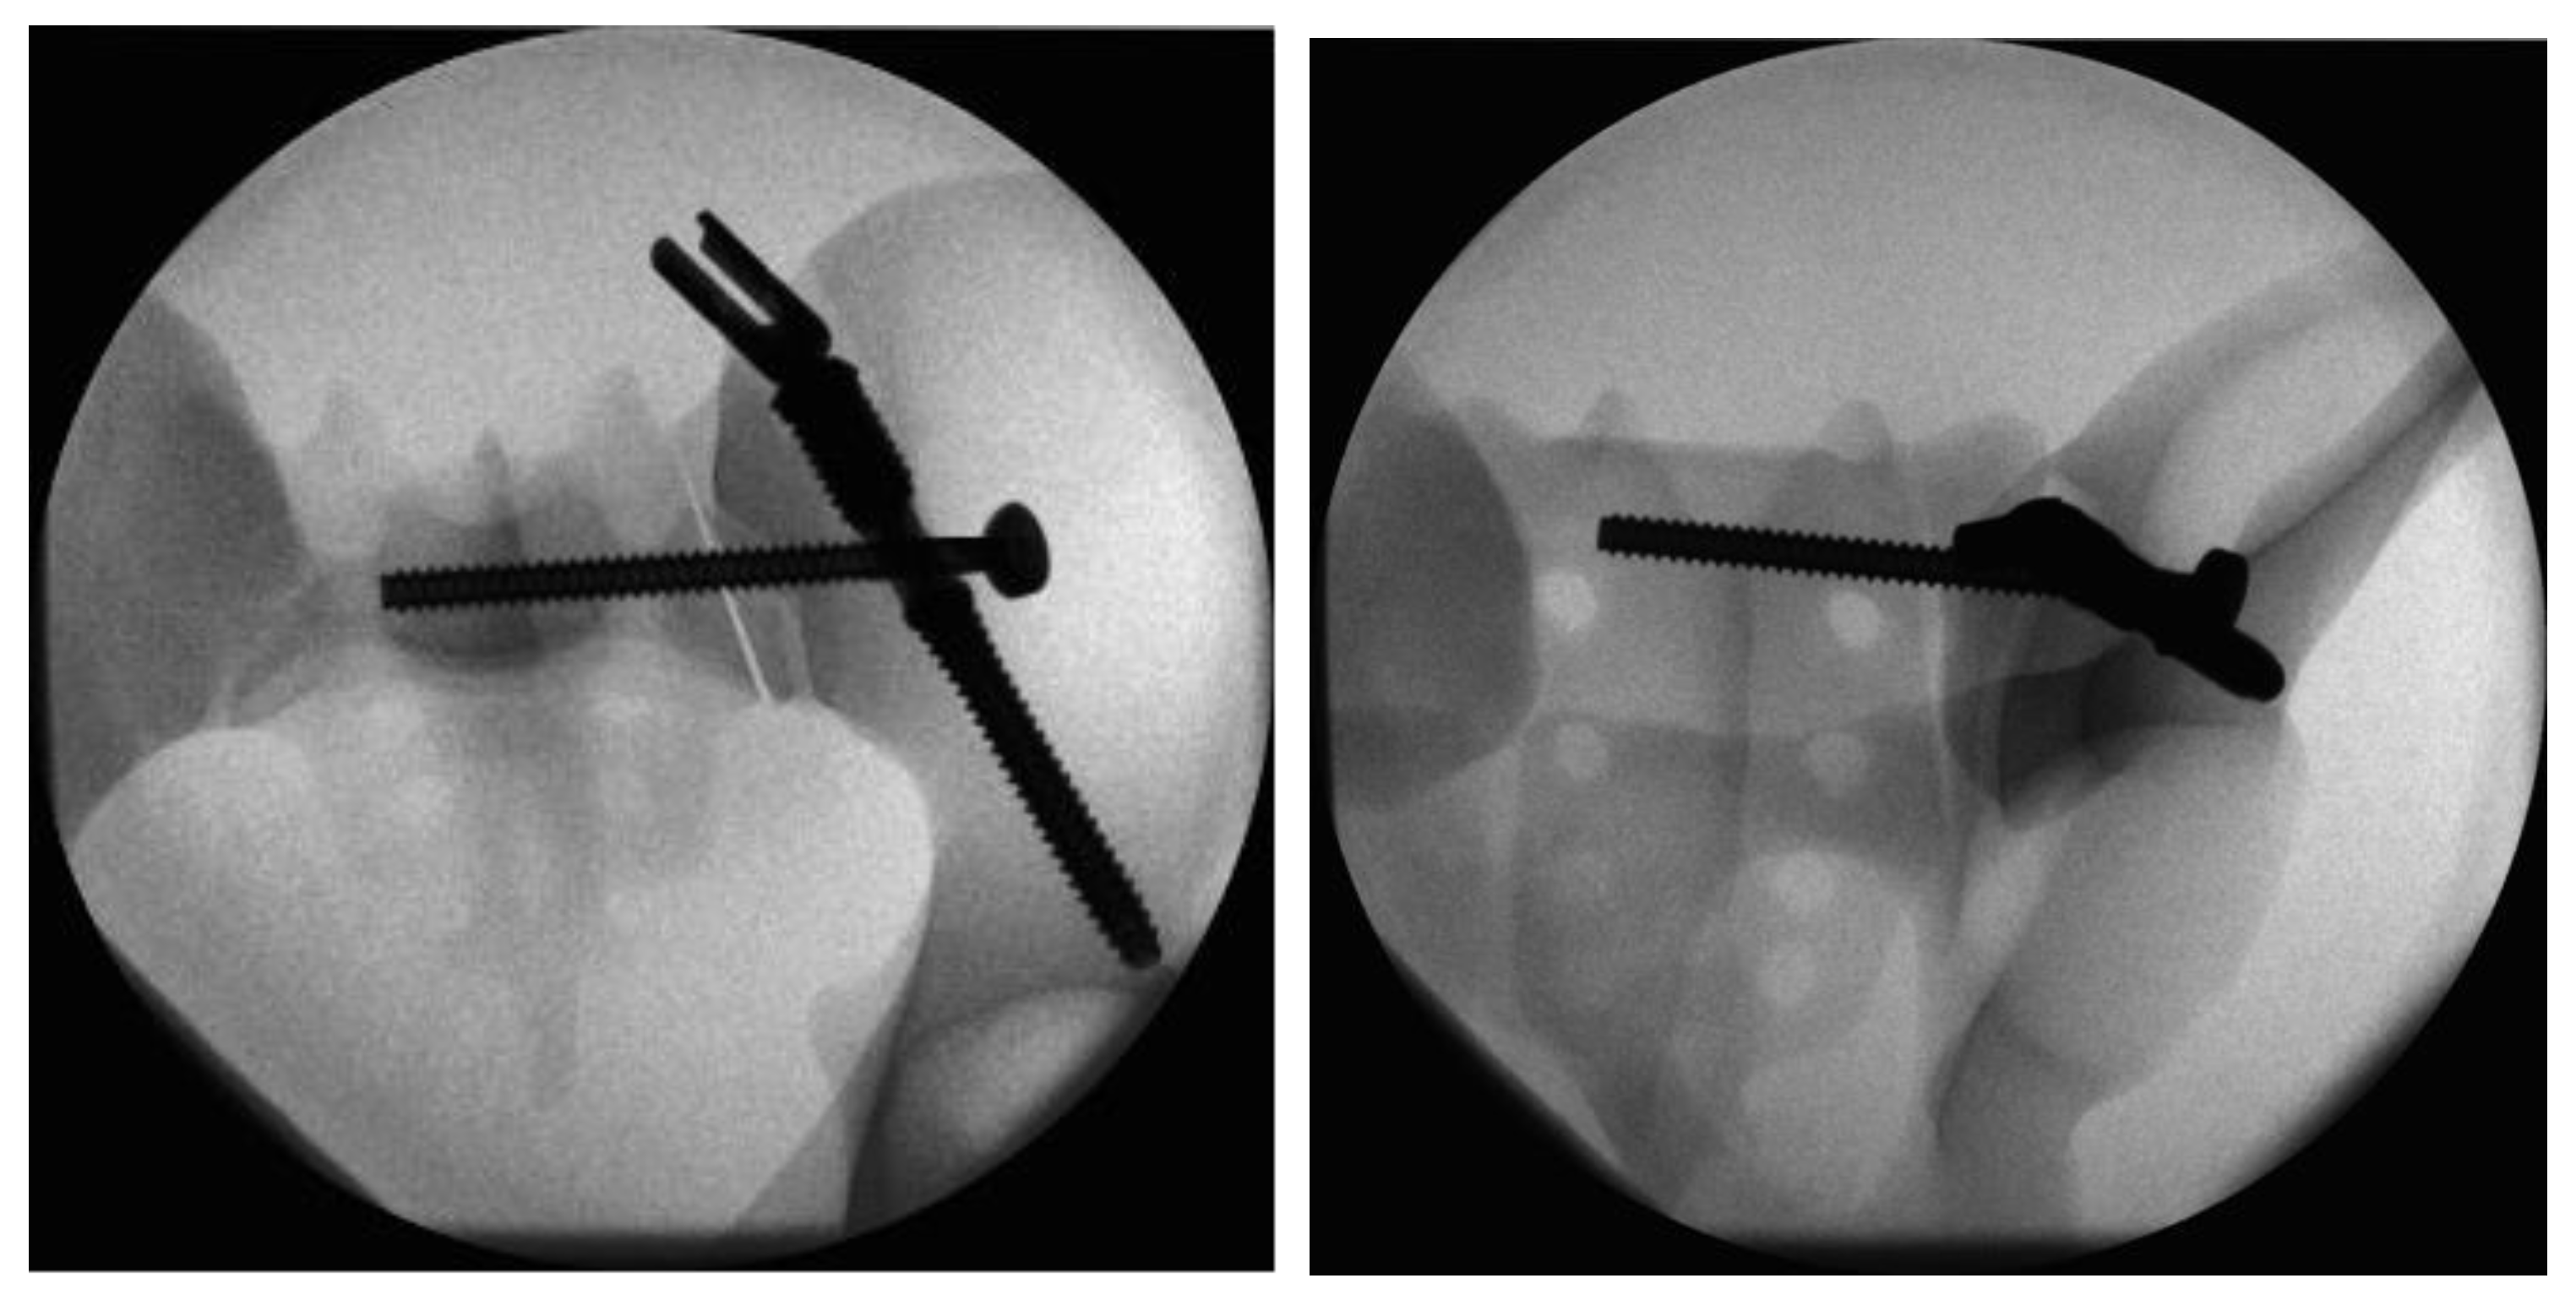

In Group I, iliac screw insertion was the first step during instrumentation of the triangular fixation system. For this purpose, a 3.2 mm guide wire was inserted into the ilium over the custom-made drill guide starting from the posterior iliac spina under radiographic guidance. Once the correct wire placement was confirmed, the screw hole was prepared by drilling and tapping. The iliac screw was then inserted to the correct depth over the guide wire. For the next step of the iliosacral stabilization, the system’s aiming arm was attached to the iliac screw. This allows for the iliac screw to interlock with the sacroiliac screw. The guide wire for the sacroiliac screw was placed with the help of the attached aiming arm under radiographic guidance. Once the optimal position had been attained, the wire was drilled over and the sacroiliac screw (length 100 mm) was inserted. After the removal of the aiming arm, the polyaxial head was connected to the iliac screw to allow for lumbopelvic stabilization (Figure 3).

Figure 3.

Radiographs in two planes of the triangular fixation system with the sacroiliac screw positioned through the fenestra of the iliac screw.

In Group II, the instrumentation was similar to Group I. First, the iliac screw was placed as described. The main difference was in the placement of the sacroiliac screw that was placed separately without the use of the aiming device of Group 1. The guiding wire for the iliosacral screw was placed under radiographic control using a custom-made drill guide. The iliosacral screw was placed next to the iliac screw in a more cranial position to the iliac screw (Figure 4).

Figure 4.

Radiographs in two planes of the conventional triangular fixation with the sacroiliac screw separate from the iliac screw in a more cranial position.